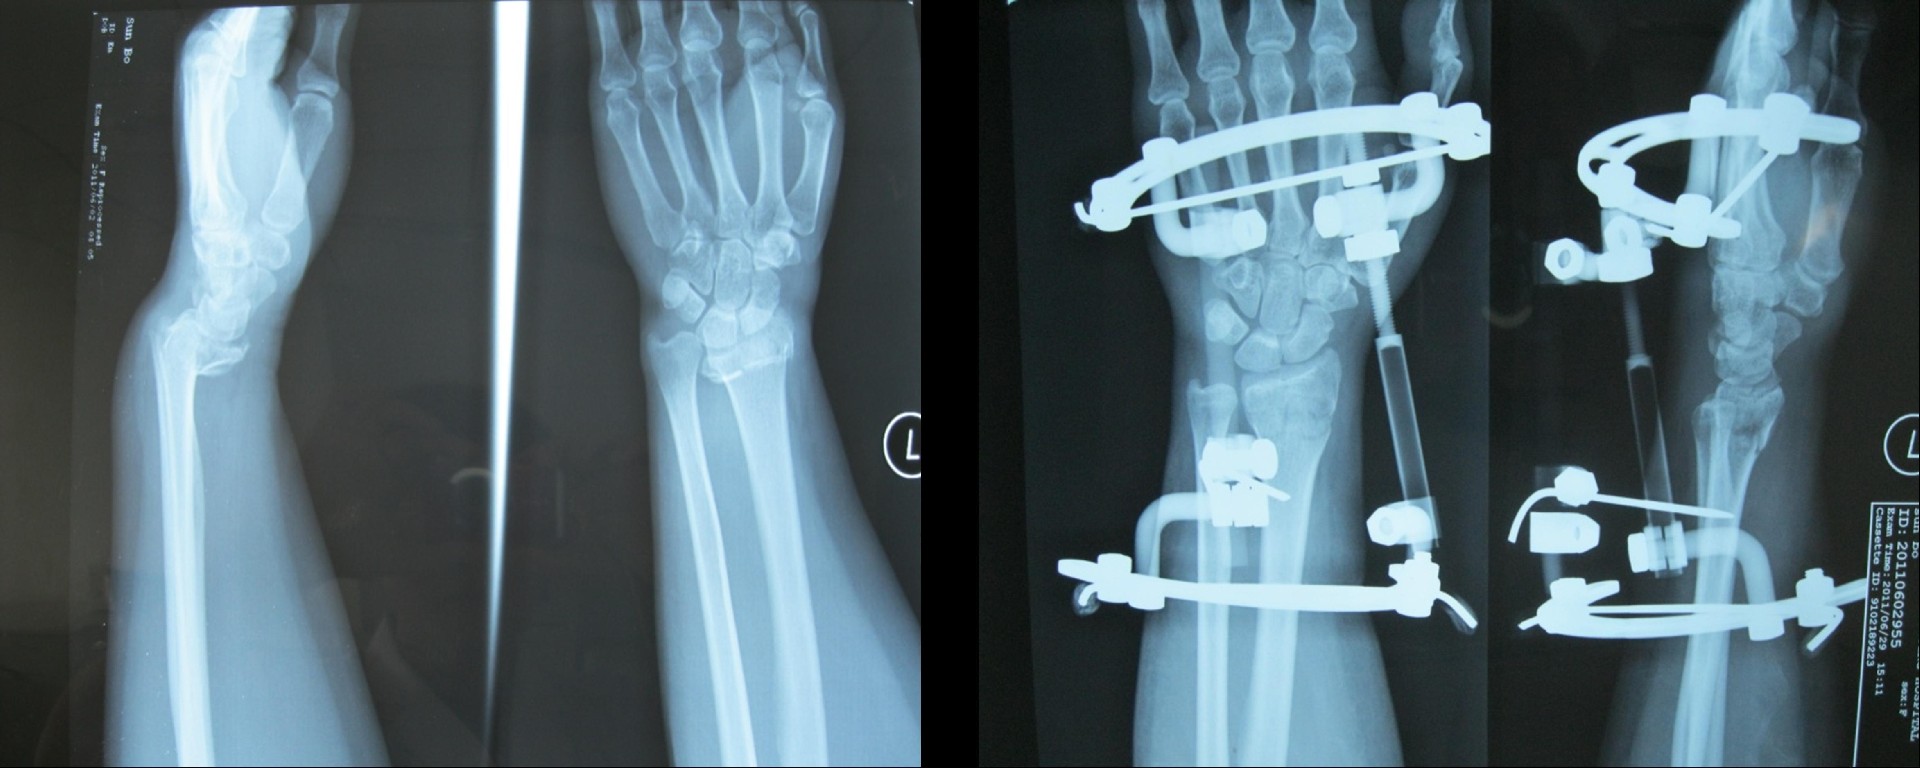

橈骨遠端骨折術前

橈骨遠端骨折術后

橈骨遠端骨折術前 橈骨遠端骨折術后

五研獨家產品組合式腕關節(jié)骨外定架,具有專利保護

組裝簡便,穿針便捷,適合各種橈骨遠端骨折及腕部矯形。斷端無X線遮擋。